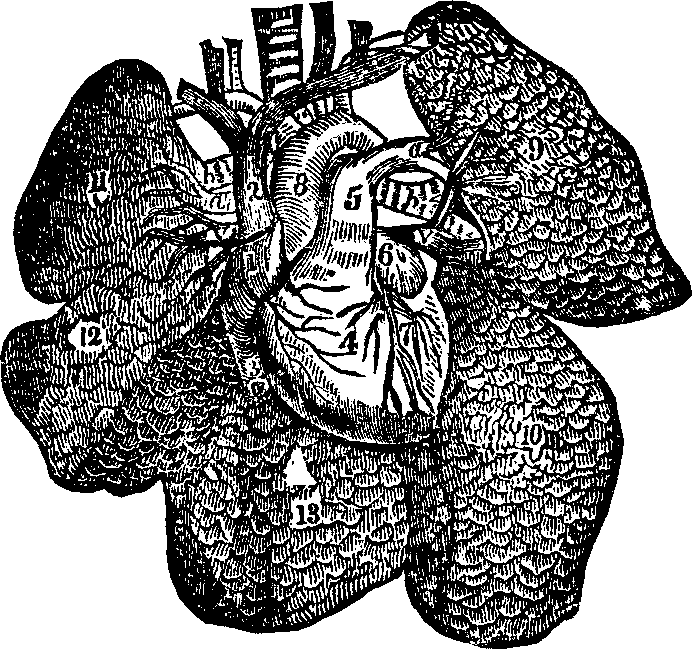

substance, and the arrangement of the pigmentary matter. C.

Transverse sections, showing the distinction between the cortical and

medullary substances, and the central collection of pigmentary matter,

sometimes found in the latter. Magnified 310 diameters.

Hairs are horny appendages of the skin, and, with the exception

of the hands, the soles of the feet, the backs of the fingers and toes,

between the last joint and the nail, and the upper eyelids, are distributed

more or less abundantly over every part of the surface of the body. Over

the greater part of the surface the hairs are very minute, and in some

places are not actually apparent above the level of the skin; but the hair

of the head, when permitted to reach its full growth, attains a length of

from twenty inches to a yard, and, in rare instances, even six feet. A hair